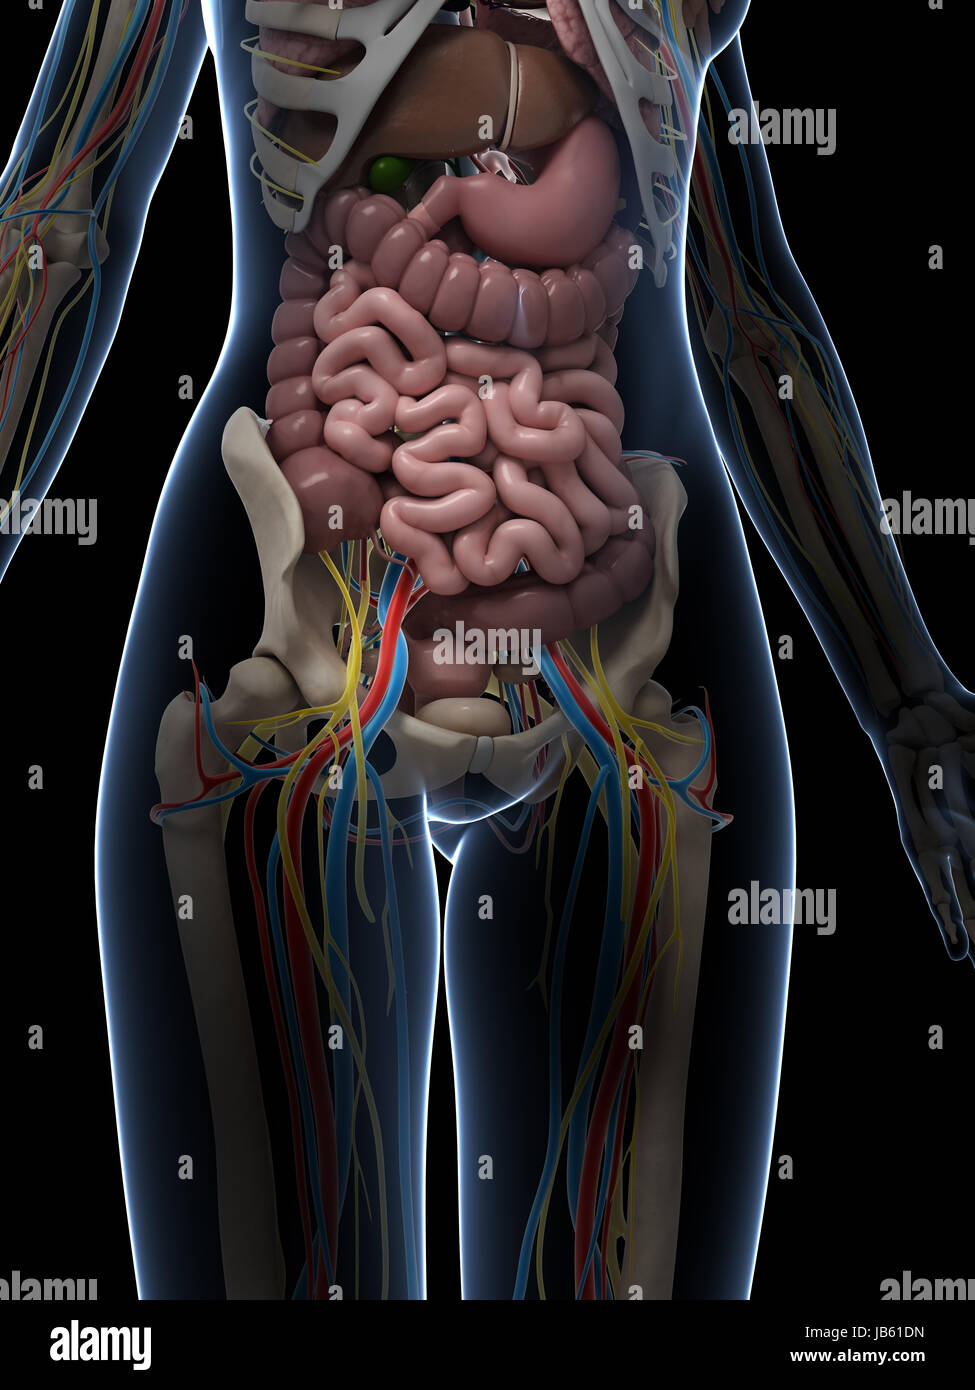

Female Torso Anatomy Diagram : Vintage 1950's Frohse Chest & Abdomen Viscera Human  Pin on Drawing Guide

Female Torso Anatomy Photograph by Pixologicstudio/science Photo Library  Female Upper Torso Anatomy - Human Female Torso Anatomy 3d model - CGStudio : Anatomy study of

Female Upper Torso Anatomy - Human Female Torso Anatomy 3d model - CGStudio : Anatomy study of  Torso Anatomy Plate French Vintage Original Print 1920's - Etsy